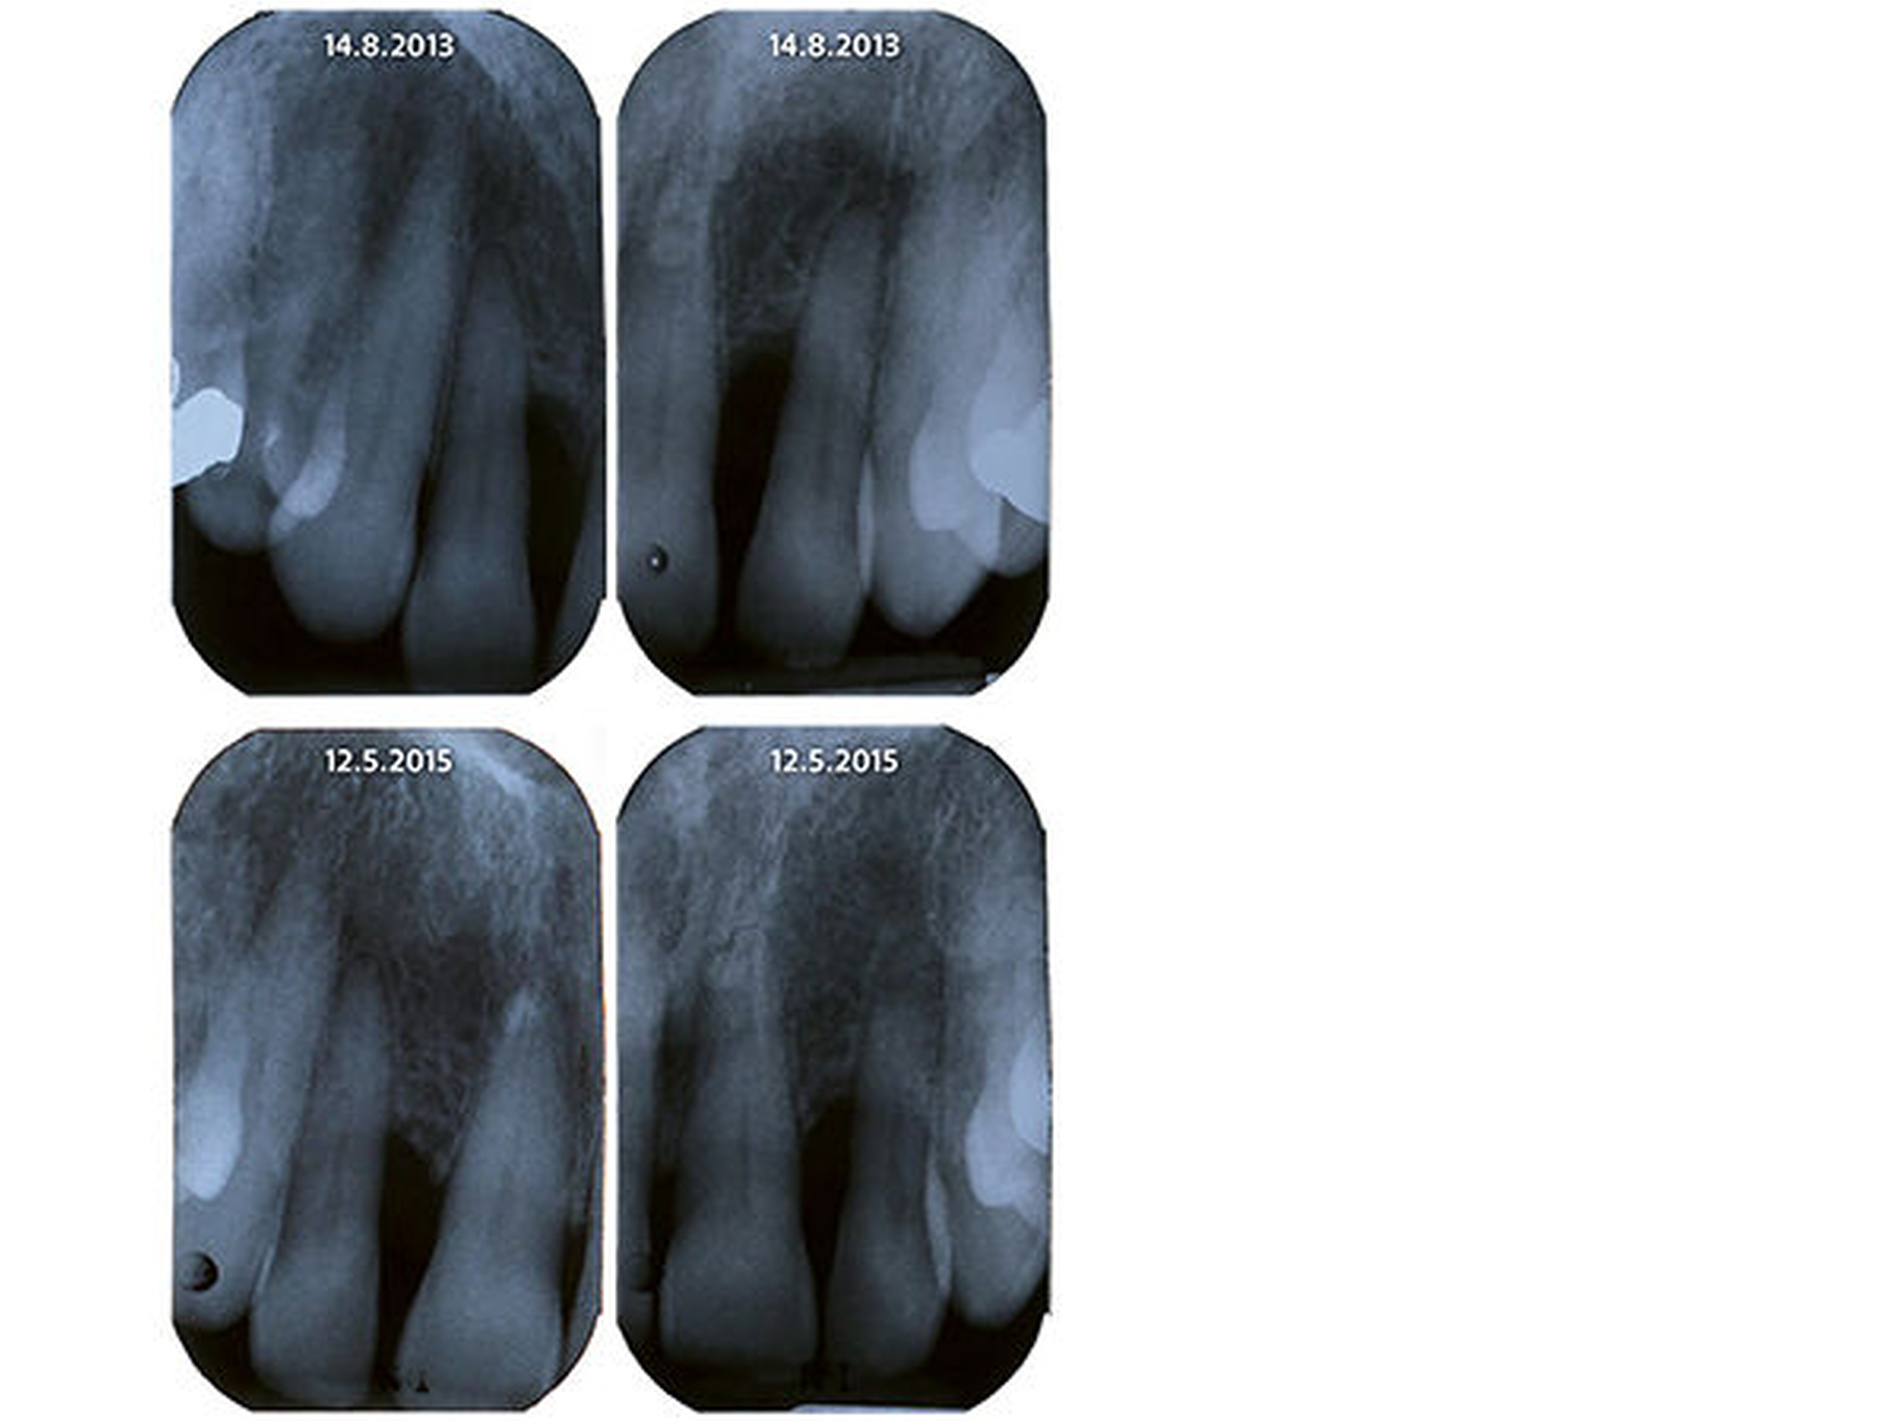

Eine 61-jährige Patientin mit einer postmenopausalen Osteoporose, einer Divertikulose, seit 2005 bekannten und im Verlauf größenregredienten Pankreaszysten sowie einer Allergie auf Neo-Citran® stellte sich aufgrund einer zwar relativ lokalisierten, gleichwohl aber schweren Parodontitis vor. Insbesondere die lateralen Inzisiven zeigten dabei Sondierungstiefen bis zu 9mm mit Suppuration/Bluten auf Sondieren (Abbildung 1 und 2), die bisher – trotz relativ guter Mundhygiene – bei verschiedenen Zahnärzten ohne Erfolg behandelt wurde.

Diese Befunde waren mit entzündlichen Veränderungen und somit mit der klinischen Präsentation und den Laborbefunden vereinbar. Aufgrund dieser Befunde wurde die Patientin auf der gastroenterologischen/viszeralchirurgischen Station des Inselspitals Bern zur weiteren Behandlung stationär aufgenommen. Unter Hydrierung, analgetischer Therapie sowie Nahrungskarenz stellte sich in der Folge eine Besserung ein und die Patientin konnte nach drei Tagen in gutem Allgemeinzustand nach Hause entlassen werden. Zahnmedizinisch zeigten die weiteren Recalls nach Initialtherapie erfreuliche parodontale Befunde, weshalb keine weiteren parodontalchirurgischen Therapien durchgeführt werden mussten (Abbildung 1 und 2).